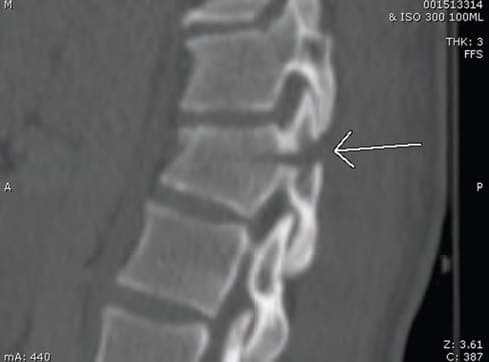

Перелом Чанса — це поперечні переломи тіла хребця (Зобр. 7-7).

Зобр. 7-7 Перелом Чанса. Рентгенограма показує перелом Чанса (поперечний перелом тіла хребця)

Вони викликані згинанням навколо осі попереду від хребетного стовпа і найчастіше спостерігаються після автомобільних аварій, під час яких пацієнт був обмежений тільки неправильно пристібнутим поясним ременем безпеки. Можливі переломи можуть бути пов’язані із заочеревинними та вісцеральними травмами живота.

Прості компресійні переломи здебільшого стабільні, їх часто лікують за допомогою жорсткого бандажа. Розривні переломи, переломи Чанса та переломи-вивихи надзвичайно нестабільні й майже завжди потребують внутрішньої фіксації.